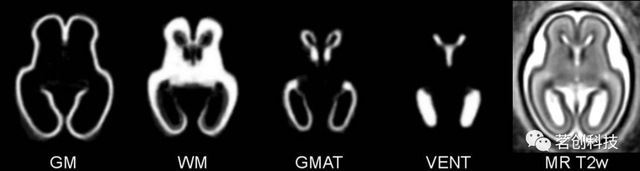

子宫内3D统计图谱

这是一个组织分布概率图谱,由14个胎龄20.57-22.86周胎儿大脑的临床MRIs构建而成。这些胎儿在出生后正常发育。该图谱包括来自T2加权模板的平均形状和强度,以及灰质、白质、生发基质和脑室的四个组织概率图。组织概率图是由手动绘制生成的。这个图谱现在已经扩展到包括一个时域来形成一个时空图谱(胎儿大脑的时空图谱)。

来源:Atlas-based segmentation of developing tissues in the human brain with quantitative validation in young fetuses.

胎儿大脑的时空图谱

这是子宫内3D统计图谱中所描述图谱的时间扩展,该图谱由40个正常发育的胎龄20.57-27.86周胎儿的大脑构建而成。该图谱包括来自T2加权模板的特定年龄平均形状和强度,以及灰质、白质、生发基质和脑室的特定年龄组织概率图。组织概率图是由手动绘制生成的。图谱提供的重要信息是特定年龄T2加权强度和组织概率。

来源:A spatiotemporal atlas of MR intensity, tissue probability and shape of the fetal brain with application to segmentation.